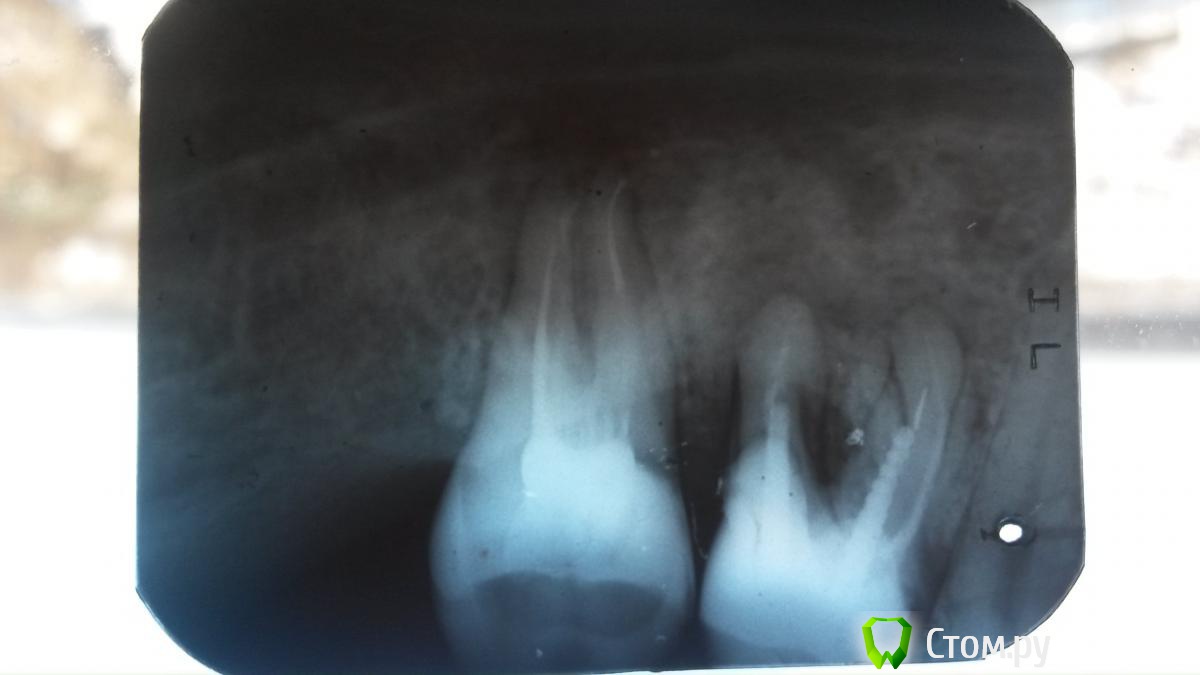

Галла Опубликовано 11 декабря, 2013 Автор Поделиться Опубликовано 11 декабря, 2013 Это свищ (выход гноя). Причина в зубе. Зуб удалять Д.д! А альтернативы никакой? Жалко всё таки лишатся своего родного. Зуб на снимке совсем плохой и не подлежит перелечиванию???? Ссылка на комментарий

Мартовский Опубликовано 11 декабря, 2013 Поделиться Опубликовано 11 декабря, 2013 Д.д! А альтернативы никакой? Жалко всё таки лишатся своего родного. Зуб на снимке совсем плохой и не подлежит перелечиванию???? Не подлежит. Чем быстрее вы эту бомбу уберете, тем лучше 2 Ссылка на комментарий